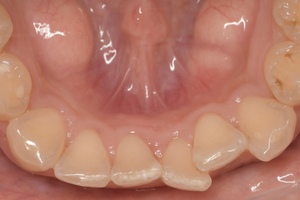

CASE 2

基本情報

| 年齢・性別 | 30代・男性 |

| 主訴 | 歯石を取りたい |

| 治療内容 | 超音波スケーラーでの歯石除去 |

| 治療期間 | 60分 |

| 治療費 | 初診料を含め約4,500円 |

| リスク・副作用 | 歯ぐきに違和感や痛みを覚える場合がある。 1週間程度、歯を磨くといつもより出血することがある。 腫れていた歯ぐきが引き締まることで歯ぐきが下がった様に見える。 歯ぐきが下がることで歯がみしやすくなることがある。 一時的に歯の動揺(ゆれ)が増す場合がある。 |